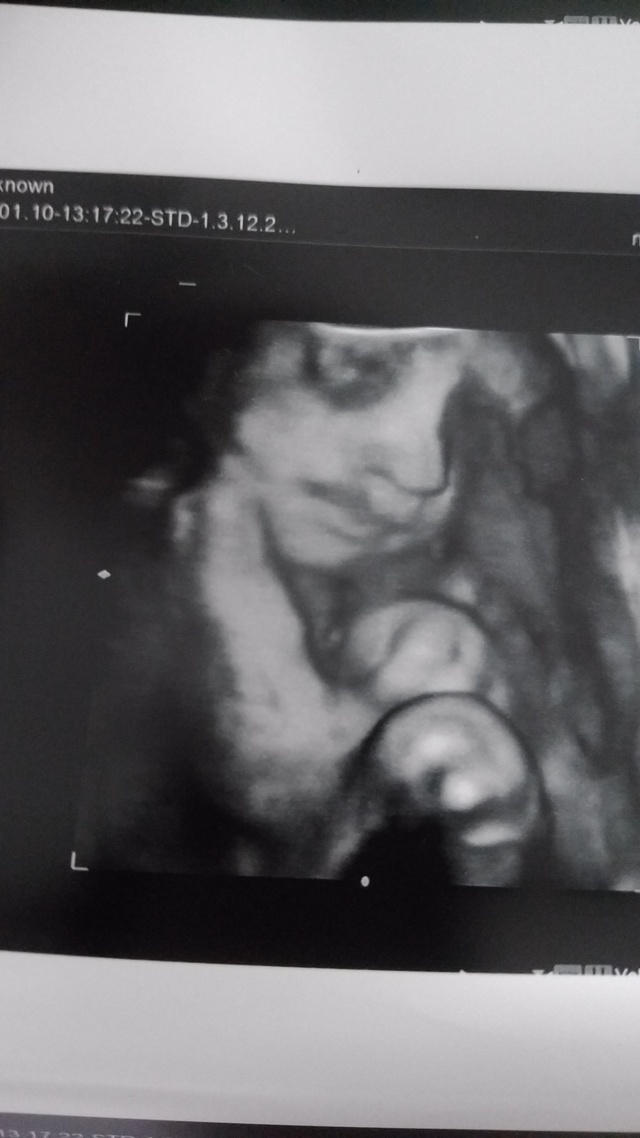

30週0日(30w0d・男の子)|mika1011 さん(26歳)

エコー写真撮影時のエピソード:

初めて4Dエコーを撮って、思っていたよりリアルで旦那さんと一緒に驚いたのを覚えています。4Dエコーで我が子の顔をはっきりと見て、お腹に赤ちゃんがいるという実感が一気にこみ上げてきて、感動で涙してしまいました(笑)